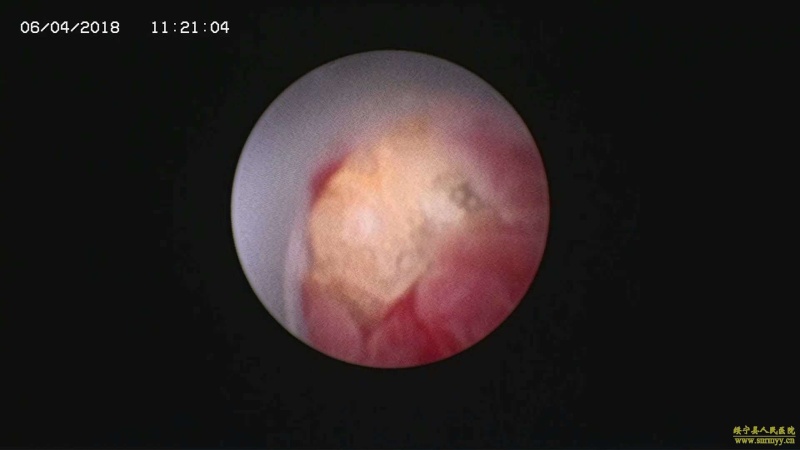

多镜联合治结石 4月6日,处于休假期间,但绥宁县人民医院泌尿外科的医护没有休息,在科主任张华生的带领下,打破常规,挑战高度,成功完成了一台复杂的结石手术。 据悉,患者姓杨,是一位60岁的男性患者,因"间断性左侧腰痛2年,再发伴尿痛2天"入院,经检查后发现患者左肾、左侧输尿管、膀胱内均有多发结石。针对这种结石,传统的手术方法至少需要开3刀,且需分期进行,使得患者痛苦大、治疗周期延长,费用也相应增高。肾结石开刀手术后劳动力会严重散失,即使采用现在流行的微创手术,常规也得分期进行,患者免不了多次手术的痛苦。为进一步减轻患者痛苦,绥宁县人民医院泌尿外科的医师们经过慎重考虑,决定打破常规,制定了多镜联合取石的手术方案。手术在4月6日顺利进行,术中联合膀胱镜、输尿管镜、经皮肾镜进行了长达70分钟的治疗,使得出血量不超过5mL且伤口仅0.5cm,一次性将患者膀胱,左侧输尿管,左肾结石全部取出。术后第五天经复查无任何结石残留,4月13日患者顺利出院。 目前,绥宁县人民医院泌尿外科在微创手术治疗各种尿路结石的技术上,己非常熟练。结石在整个邵阳地区发病率都很高,平常多喝水,每天饮水2000ml以上,调节饮食生活习惯,坚持锻炼可以有效预防结石发生,定期的健康体检也是预防结石的有效措施之一,可以早期发现结石,及时治疗。(图文 付志峰 编辑 谢雅玲) 图为:泌尿外科主任张华生、副主任付志峰进行手术时场景 图为:膀胱结石显象→手术碎石中显像→膀胱结石碎石后显像 图为:输尿管结石显像→输尿管结石碎石后显像 图为:肾结石显像→取出的肾结石标本 图为:术中建立穿刺通道 图为:术后留置的引流管 图为:术后伤口情况 |